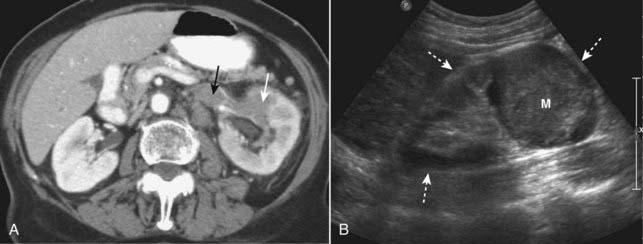

Renal Cell Carcinoma (Hypernephroma)

image Renal cell carcinoma is the most common primary renal malignancy in adults. Solid masses in the kidneys of adults are usually renal cell carcinomas. They have a propensity for extending into the renal veins, into the inferior vena cava and producing nodules in the lung.

image When they metastasize to bone, they are purely lytic and often expansile.

imageRecognizing renal cell carcinoma on CT:

image A dedicated CT scan for renal cell carcinoma usually consists of images obtained before and after intravenous contrast administration.

image Ranging from completely solid to completely cystic, renal cell carcinomas are usually solid lesions which may contain low-attenuation areas of necrosis. Even though renal cell carcinomas enhance with intravenous contrast, they still tend to remain lower in density than the surrounding normal kidney.

image Renal vein invasion occurs in up to one in three cases and may produce filling defects in the lumen of the renal veins (Fig. 18-38A).

image On ultrasound, smaller renal cell carcinomas are usually hyperechoic; as the lesion increases in size and undergoes necrosis it may be hypoechoic. Its wall, however, should be thicker and more irregular than a simple cyst (Fig. 18-38B).

image

Figure 18-38 Renal cell carcinomas CT and US.

A, There is a low-density mass involving the anterior portion of the left kidney (solid white arrow). The tumor is seen to extend directly into the left renal vein (solid black arrow), a propensity for renal cell carcinomas. B, Sagittal ultrasound on another patient with renal cell carcinoma shows an echogenic mass (M) occupying the mid portion of the kidney (dotted white arrows).